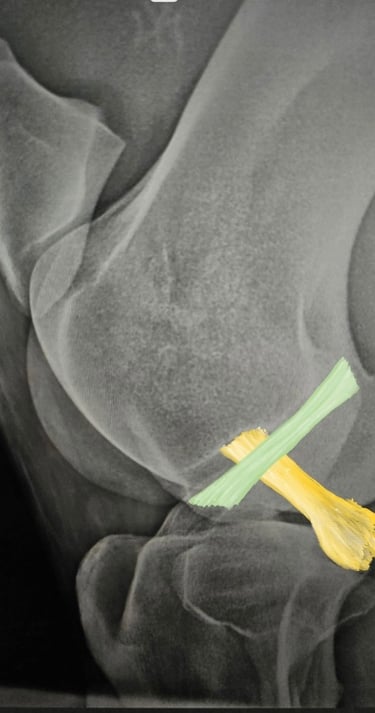

BLOQUEOS DIAGNOSTICOS